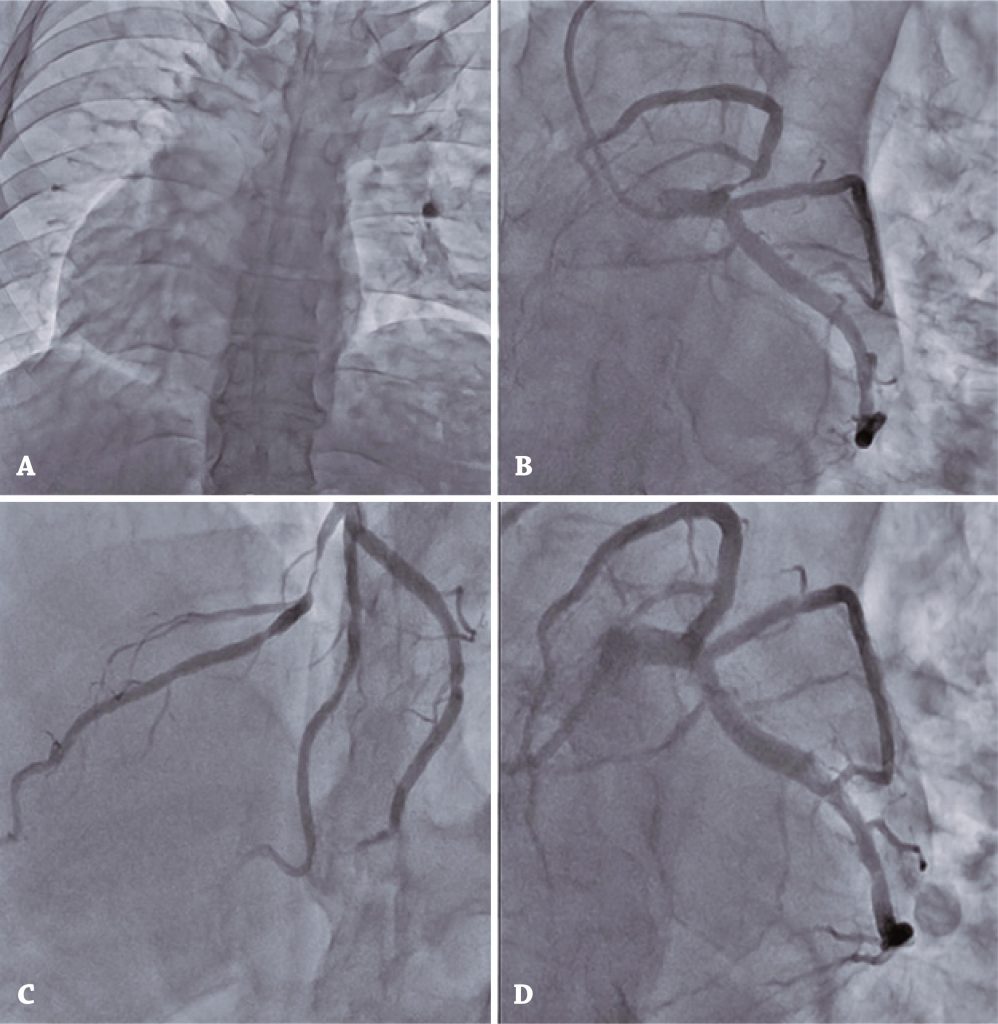

Figure 2

Coronary cineangiography and percutaneous coronary intervention. (A) Dextroposition. (B/C) Severe proximal lesion of the left anterior descending artery. (D) Result of percutaneous coronary intervention with stent placement.